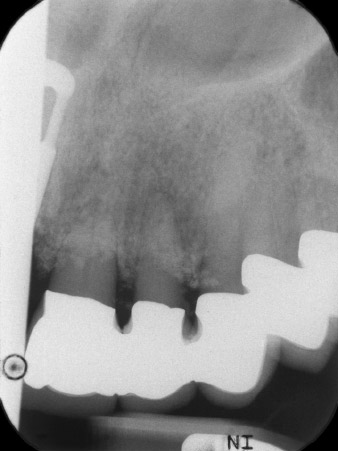

Bei der Erstvorstellung sind die Zähne 21, 22 und 23 mit 19 Jahre alten verblockten Kronen versorgt. Sie sind über ein Geschiebe mit Implantaten an den Positionen 12/11 verbunden (vgl. Abb. 2). Das Röntgenbild zeigt einen horizontalen Knochenverlust um die Zähne 21 und 22 (Abb. 1).

Nach primärer Abheilung werden die Weichgewebe mithilfe der basal unterfütterten Brücke ausgeformt. Zwei Monate später erfolgt die Freilegung mit einem leicht palatinal gelegten Kieferkammschnitt (Abb. 2).

Der Alveolarknochen erweist sich an Position 22 als ausreichend dimensioniert. Die Abbildungen 2 und 4 zeigen die Implantatbett-Aufbereitung, den Gewindeschnitt und die Implantation mit dem Implantmed.